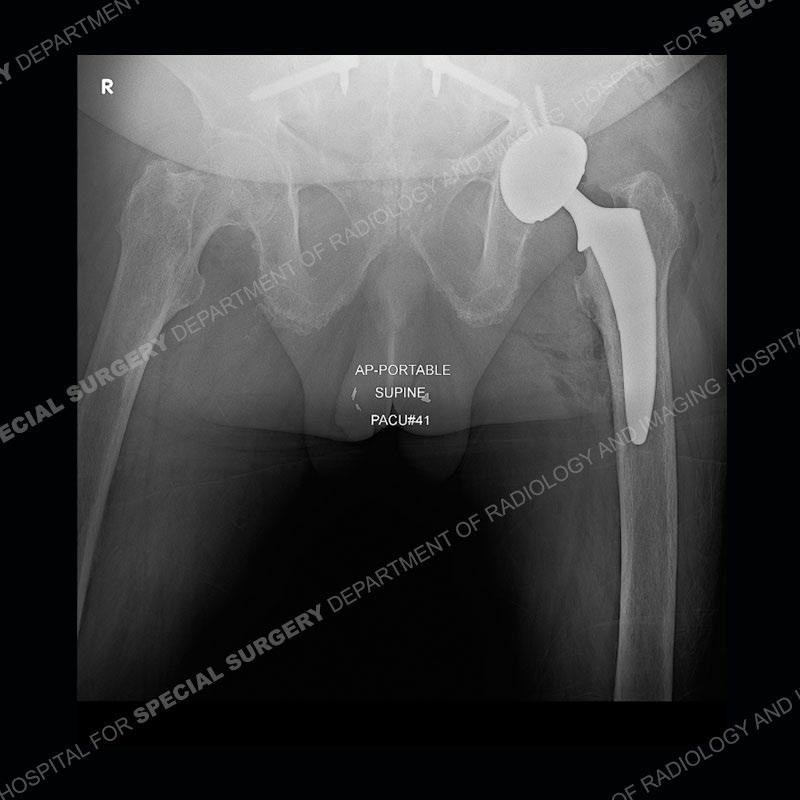

There is severe degenerative change of the left hip. The lumbar and thoracic spine show calcification of the intervertebral discs, loss of disc space, and bulky bony bridging across the disc spaces. Of important note is that the sacroiliac joints are open. They show advanced degenerative changes but not findings of an inflammatory arthritis. Bilateral knee arthroplasties are present and there are severe degenerative changes of both glenohumeral joints.

In comparison to ankylosing spondylitis (AS) where there are thin syndesmophytes of the outer annulus, this bony bridging tends to be bigger and bulkier. In addition, at this stage of AS the sacroiliac joints would be fused, but in ochronosis as seen here, the SI joints are open although with severe degenerative changes. No erosions are present of the SI joints, just advanced degenerative changes. This patient was treated with a left total hip arthroplasty and the black deposition of oxidized homogentistic acid of the cartilage is well shown.